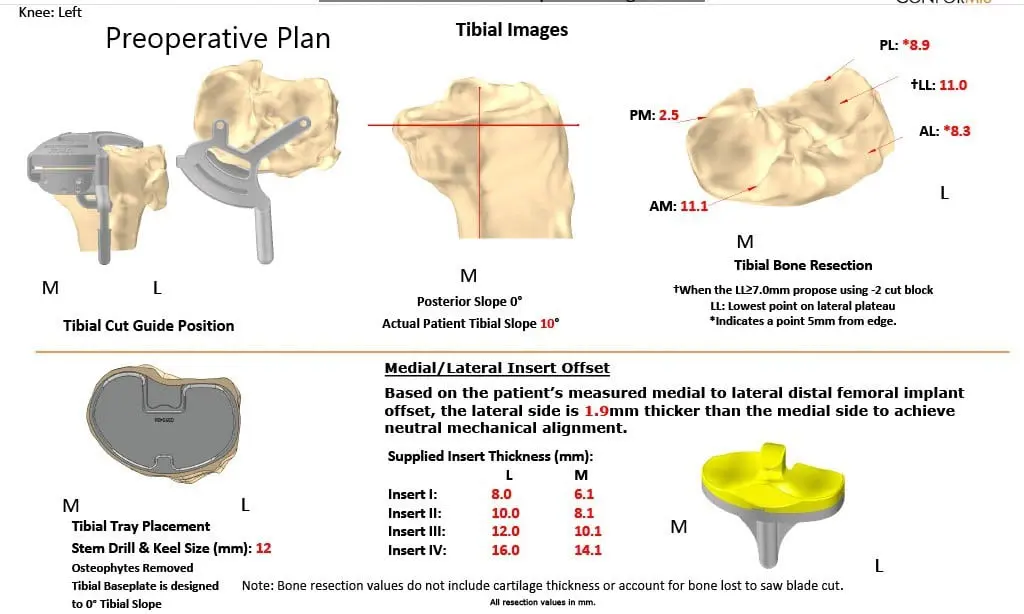

The patient had a preoperative CT scan for assessing his biomechanics and anatomy to aid in bone preserving surgery. The images were used to construct custom patient-specific implants and instruments. Unique 3D printed cutting blocks are used to preserve maximum bone. Preoperative plans are created using the 3D images to ensure correct alignment and prevent implant mismatch which is common with traditional implants.

Complete Orthopedics patient-specific surgical plan for a left custom knee replacement in a 70-year-old female.